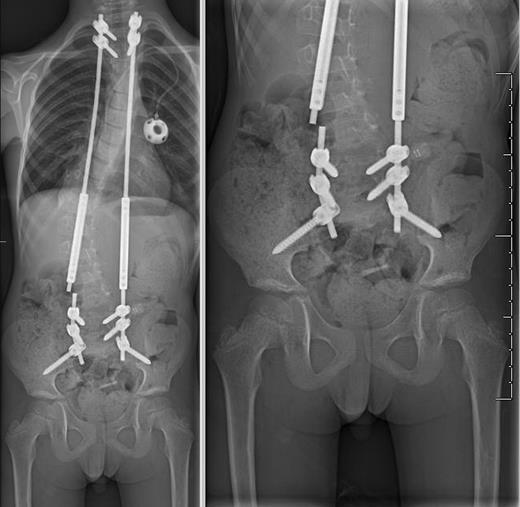

At his 1-month postoperative visit, the patient reported an interval decrease in his neck pain. However, 5 months after growing rod placement, the patient was seen in clinic for increased mid-thoracic back pain and subjectively increased prominence of his right thoracic muscle prominence. X-rays revealed a complete break in the right-sided rod at L3–4 with 5 mm of lateral displacement of the proximal fragment (Fig. 4). He subsequently underwent replacement of the fractured rod and lengthening of the entire construct.

AP plain films demonstrating complete fracture of the right-sided growth rod with 5 mm of lateral displacement of the proximal fragment relative to the distal fragment.

He had three total lengthening procedures in the first 14 months since placement of the growing rods with improvement in his scoliotic curvature to 22 degrees (Figs 2C and 3B). Eighteen months after insertion of his growing rod construct, he developed hardware infection requiring hardware removal. He is scheduled to undergo definitive fusion in the near future. He has returned to his initial independent functional status with minimal gait abnormality (McCormick Grade II) and is able to participate in activities such as biking and skateboarding. He is now 10 years old.